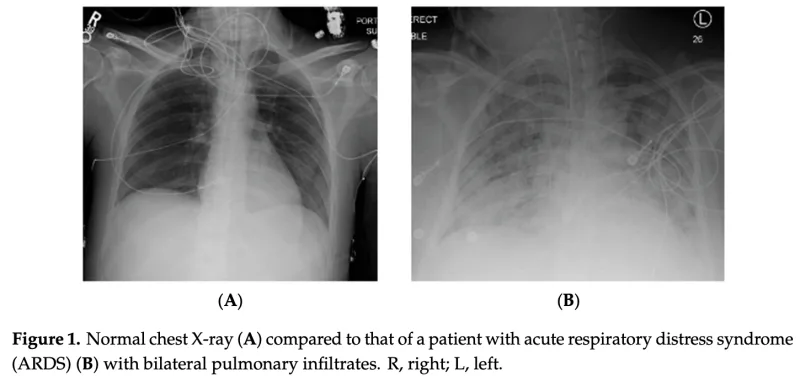

胸部X線写真を撮ったところ, 昨日より胸水は減っていましたが, 両肺が真っ白になっており, 急性呼吸促迫症候群(Acute Respiratory Distress Syndrome: ARDS)と診断.